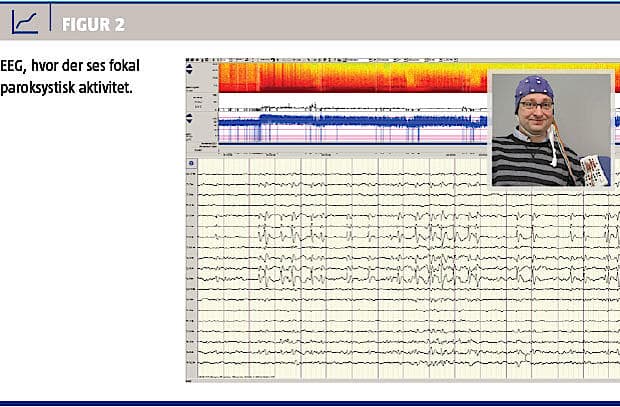

EEG er måling af hjernens elektriske aktivitet fra et antal elektroder, der er placeret på patientens skalp (standard: 21 elektroder) (Figur 2). Ved metoden kan man se tegn til epilepsi både mellem anfaldene og under anfald. Sensitiviteten kan øges fra 35-50% ved første EEG til 80-90% ved gentagne EEG’er med relevante provokationer som f.eks. søvndeprivation [4].